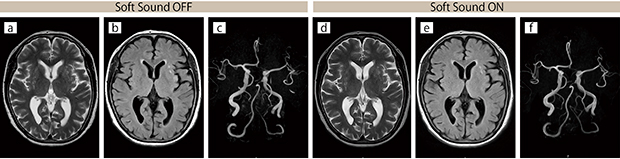

■臨床例2:頭部,同一患者比較(症例なし)

頭部撮像におけるSoft Sound OFF(a 〜c)/ON(d 〜f)の比較。

撮像時間はほぼ同等,画質は同等との評価。

a:T2 WI,AX,TR/TE = 3580 / 84,2 : 08

b:FLAIR,AX,TR/TE = 10000 /96,2 : 41

c:3D-TOF MRA,TR/TE = 23 / 6.9,4 : 19

d:T2 WI,AX,TR/TE = 3910 / 84,2 : 25

e: FLAIR,AX,TR/TE = 10000 / 96,2 : 41

f:3D-TOF MRA,TR/TE = 23 / 6.9,4 : 19